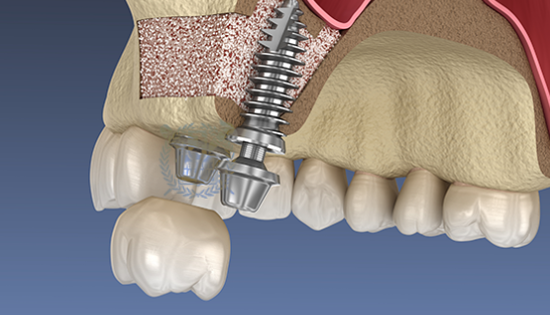

• 04

임플란트 매식체 식립

잔존하고 있는 잇몸뼈의 양에 따라 뼈이식과 동시에 임플란트 식립하기도 하고 6-9개월 후 식립하기도 합니다.

부족한 잇몸뼈를 이식하는 시술로 상악동에 있는 얇은 막을 들어 올려 막 아래로 뼈이식을 해서 보강하는 방법입니다.

뼈이식으로 높이를 확보하게 되면 임플란트를 식립해도 상악동을 건드리지 않고

임플란트의 잇몸뼈와 골유착이 잘 되어 안정적으로 시술 할 수 있습니다.

상악동거상술 시술과정

상악동거상술은 고난도 수술로 임플란트 수술 경험이 많은 의료진에게 받는 것이 중요합니다.